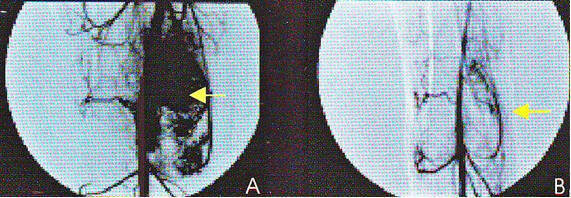

7. Дигитальная субтракционная ангиография 22-летнего пациента после единственного сеанса HIFU по поводу остеосаркомы дистального отдела бедра.

А) до HIFU на ангиограмме отчетливо визуализируется капиллярная сеть опухоли (стрелка). Через 3 месяца после HIFU капиллярная сеть на изображении отсутствует, что подтверждает абляцию опухоли (стрелка).